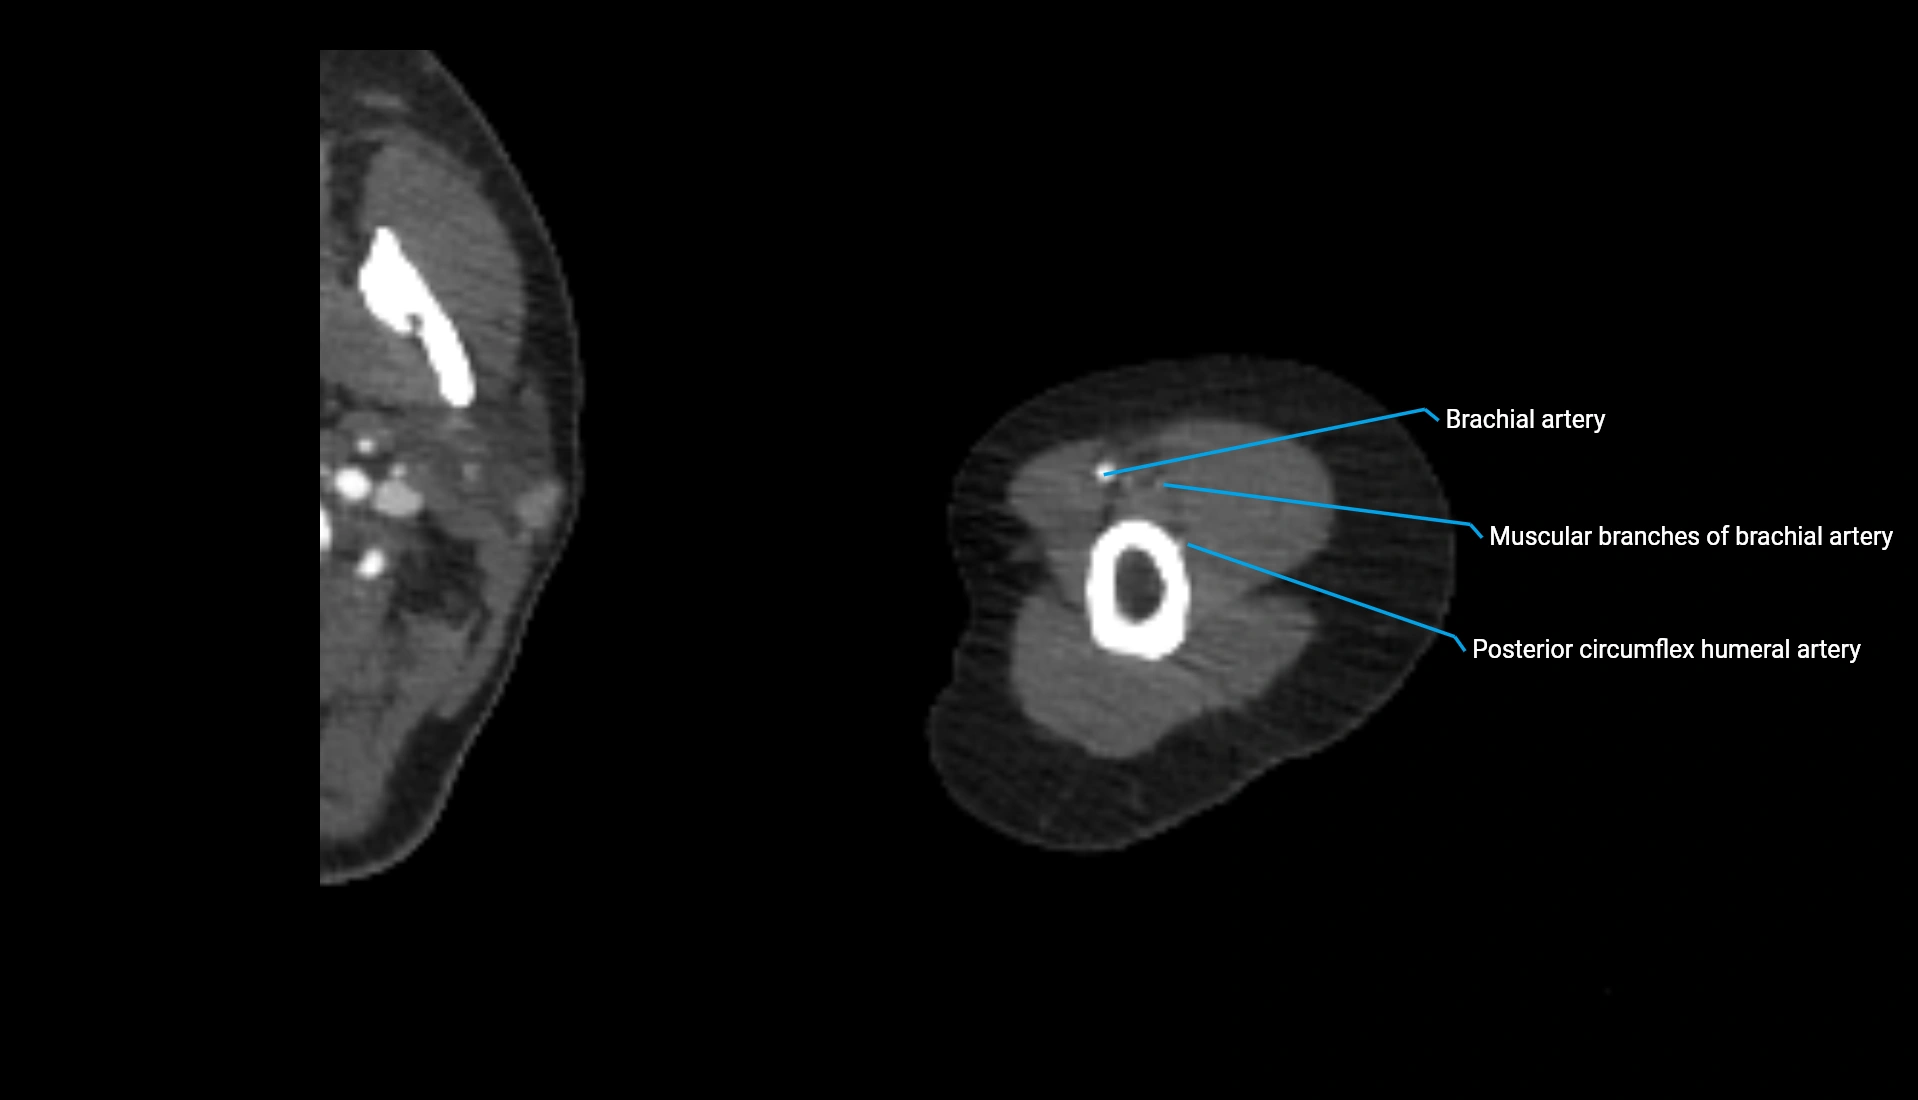

CT Appearance

Non-Contrast CT:

• Cortex: High-density, sharply defined

• Subchondral bone: Dense cancellous matrix

• Articular surface: Smooth concave contour articulating with the capitellum

• Excellent for evaluating bone integrity, alignment, and subtle fractures